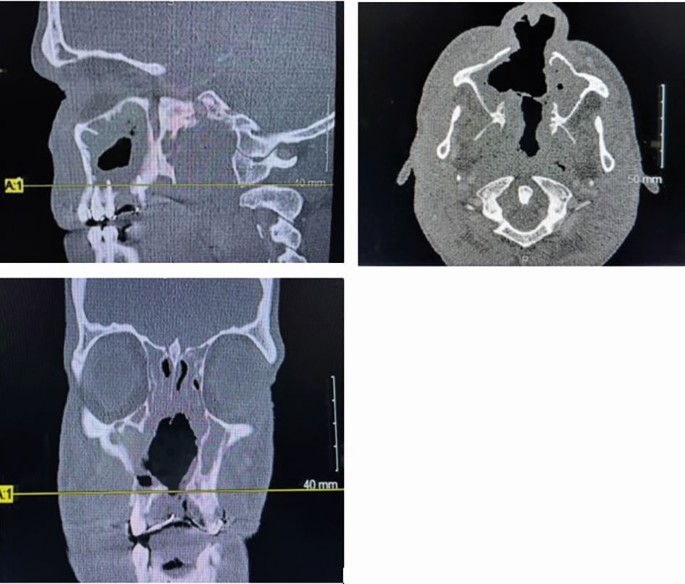

The presence of ANCA raised suspicion of systemic vasculitis. The patient was referred to the immunology department in St James's Hospital, Dublin, for concurrent care. Subsequent investigations included a computed tomography (CT) head extension of the CIMDL into the maxillary sinuses but no involvement of the orbital region (Fig. 5). Repeat blood investigations showed consistently high CRP, IgA, IgG and a positive c-ANCA with elevated levels of anti-PR3 antibodies. Attempts were made to link the patient with an addiction services program, but they declined help on multiple occasions. Repeated urine toxicology demonstrated continued use of cocaine despite the patient reporting abstinence.

Head and neck CT for Case 2, highlighting the extent of the CIMDL

Additional investigations for destructive midface defects include radiological imaging and laboratory tests, including bloods and histological assessment of sample tissues. Imaging of CIMDLs is often appropriate in cases of extensive destruction to determine the degree of spread and tissues affected. Modalities include CT and MRI (magnetic resonance imaging), the former being more appropriate for assessment of bony erosion.23 Chest x-ray may be necessary to exclude tuberculosis or GPA, which was ordered in Case 2. Laboratory investigations useful for the diagnosis of CIMDLs include a FBC, CRP and various markers of systemic inflammation of blood vessels, including ANA (antinuclear antibody) for lupus. Serology may be justified if a fungal or bacterial cause is suspected.